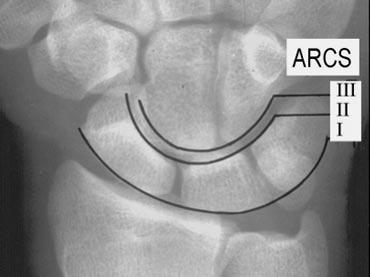

Các cung cổ tay

Bước tiếp theo là quan sát ba cung cổ tay: các đường cong trơn nối liền các bề mặt của các xương cổ tay như được minh họa ở hình bên trái.

Cung thứ nhất là một đường cong trơn phác thảo các mặt lồi phía gần của xương thuyền, xương nguyệt và xương tháp.

Cung thứ hai đi theo các bề mặt lõm phía xa của các xương tương tự, và cung thứ ba đi theo các đường cong phía gần chính của xương đầu và xương móc.